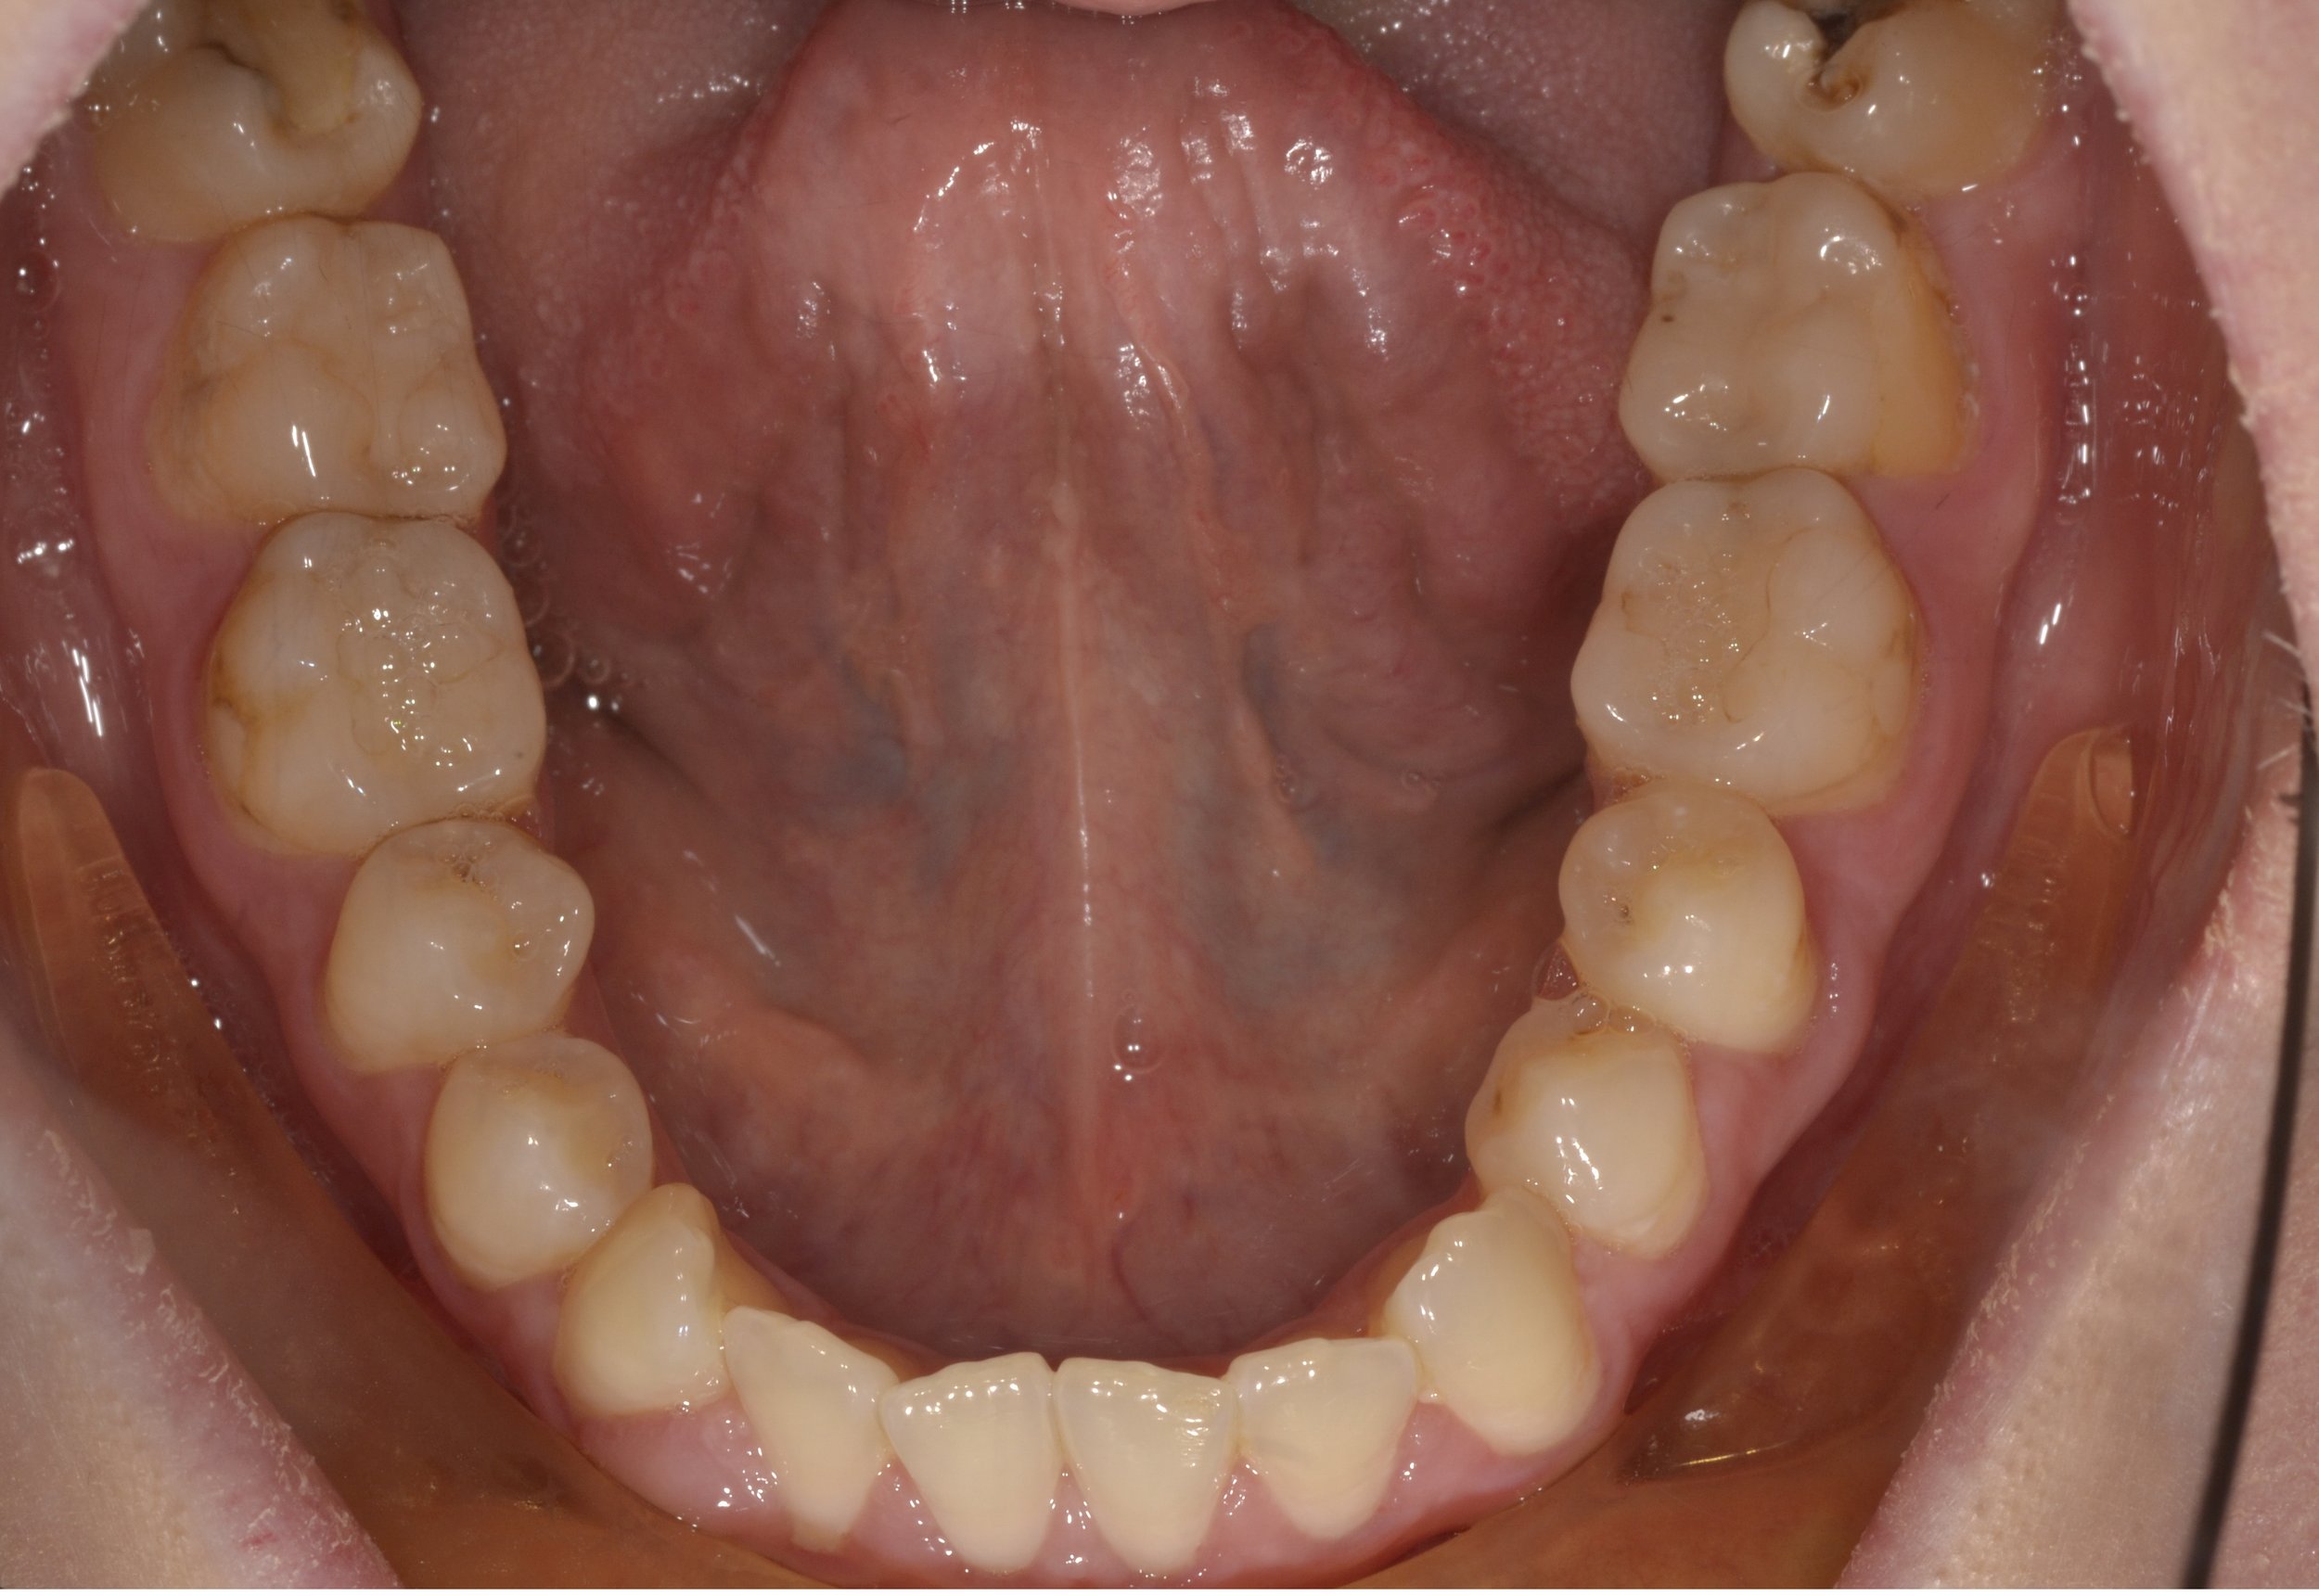

25-year old female referred to improve facial appearance and occlusion.

Findings:

• Maxilla hypoplastic in an antero-posterior/transverse plane.

• Mandible prognathic and asymmetric to the right.

• No incisal show at rest.

• Anterior open bite: contact on molars only.

• Upper arch canted (lower on the right).

• Severe upper crowding and undersized upper incisors (Bolton’s discrepancy).

• Crossbite due to skeletal positions.

PRE TREATMEnT